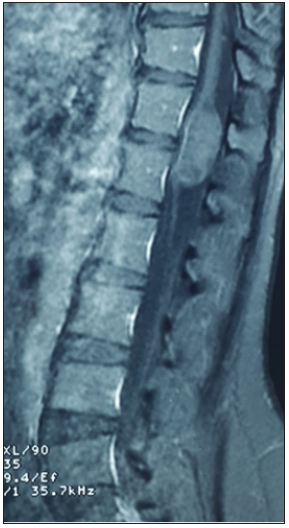

A 37-year-old woman presenting with low backache, and progressive weakness of both lower limbs for 5 months. On clinical examination, she had features of a conus medullaris syndrome with grade 4 power in both lower limbs, positive Babinski sign bilaterally, while abdominal reflexes and anal tone were normal without tuft of hair or a patent dermal sinus tract. A magnetic resonance imaging MRI showed cord expansion at the tip of the conus medullaris with a heterogeneous lesion hyperintense on T1 and hypointense on T2 images. In addition, contrast enhanced images with gadolinium revealed an intramedullary lesion at T12 L1 segment (Figure 1). After laminectomy, a midline myelotomy was performed and revealed a whitish and yellowish mass with a well-defined adherent capsule to spinal tissue followed by micro-dissection of the cyst wall allowing complete removal of caseous cystic contents with adequate conus decompression (Figure 2). Pathological examination confirmed the diagnosis of dermoid tumor, showing stratified squamous epithelial cells with underlying fibrous connective tissue containing hair follicles, keratin and sebaceous glands. The patient recovered well from the procedure, her back pain had not recurred, and she remained independent postoperatively.

Figure 1b:

Figure 1c: Spinal MRI sagittal T1 (a), T1 postcontrast (b) and axial T2 (c) showing an heterogenous lesion hyperintense T1, hypointense T2 of the conus at T12 L1 level.